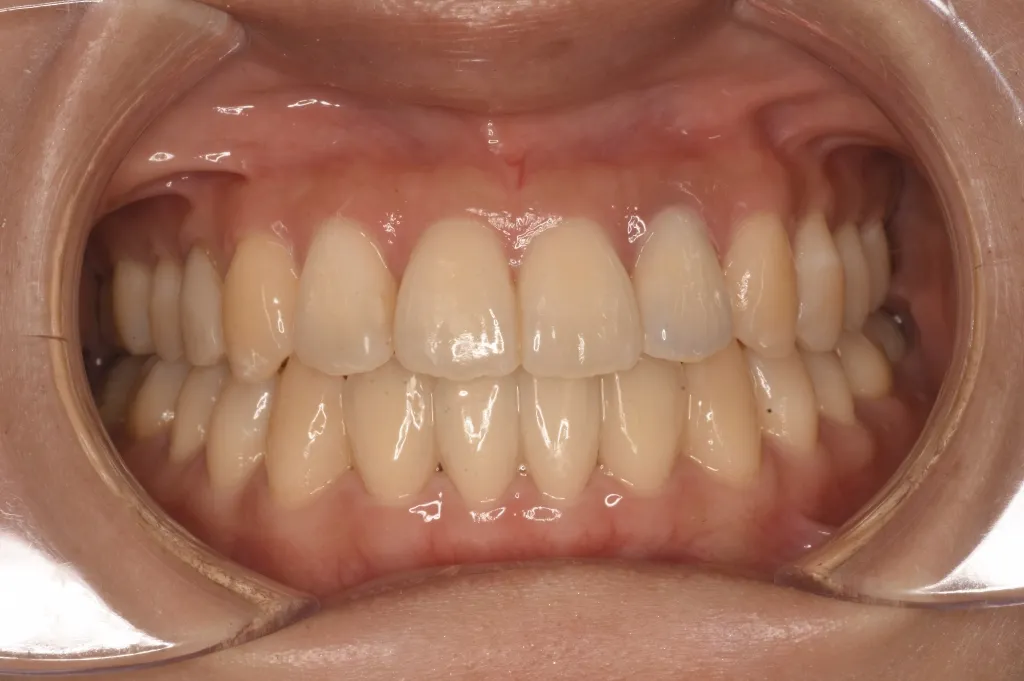

• 治療後

治療後

治療方法 インビザラインを用いたマウスピース矯正を行いました。 アタッチメントあり、顎間ゴム使用。 通院頻度:5ヶ月ごと ※症例により異なります

治療期間 1年4ヶ月(通院頻度5ヶ月に1度程度)※症例により個人差があります 手術なし、マウスピース矯正のみで開咬の改善が可能でした。

患者さんの感想 地元の歯医者では手術をしないと治らないと言われたオープンバイトでしたが、インスタグラムでこちらの歯科で私と同じ症例をマウスピースで矯正されていたのでこちらを選びました。無料相談から丁寧にしていただき、治療計画も分かりやすかったです。遠方から来ていたこともあり、5〜6ヶ月に1回の来院で良いように調整してくれたので、続けやすかったです。治療も思った以上に早く終わり(約1年半)、歯並びから噛み合わせまでしっかり調整してもらったのでとても満足です。